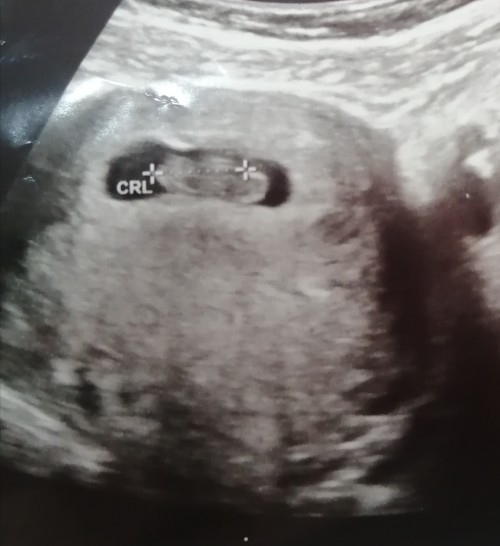

erkek bebek kesesi sekli nasildir keseye gore cinsiyet tahmini